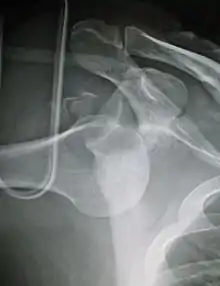

| Anterior dislocation of the left shoulder. | |

In over 95% of shoulder dislocations, the humerus is displaced anteriorly.[7] In most of those, the head of the humerus comes to rest under the coracoid process, referred to as sub-coracoid dislocation. Sub-glenoid, subclavicular, and, very rarely, intrathoracic or retroperitoneal dislocations may also occur.[8]

Anterior dislocations are usually caused by a direct blow to, or fall on, an outstretched arm. The person typically holds his/her arm externally rotated and slightly abducted.

An anterior dislocation of the shoulder